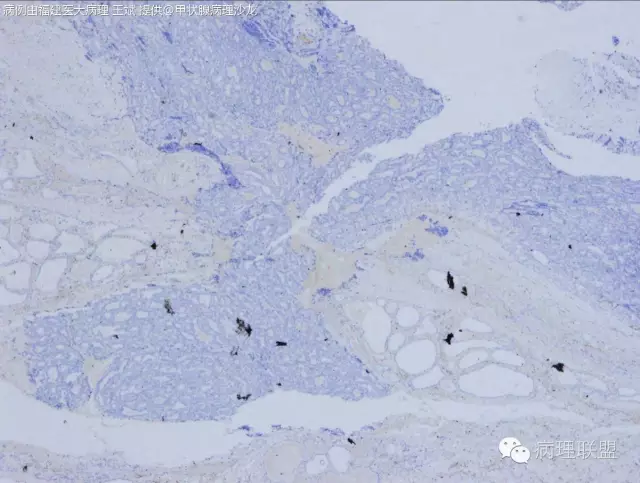

如果楞要分的话,可以染染CD56试一试

CD56、Galectin3、HMBE-1阴性,CK19灶阳

CD56

CD56区别FTC和PTC吗?

CK19

GGALECTIN3 和HMBE1 均为阴性